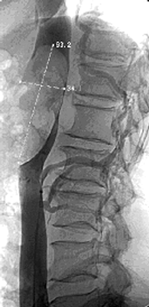

МРТ занимает важное место в диагностике объемных образований почек. Особенно это касается обследования больных с выраженным нарушением почечной функции, аллергическими реакциями на йодсодержащие контрастные растворы, противопоказаниями к ионизирующему излучению. Возможность получения многопланового изображения в различных плоскостях имеет большое значение для определения происхождения первичной опухоли, когда данные РКТ неоднозначны. Несмотря на высокую разрешающую способность, возможность многоплановой визуализации и оценки васкуляризации без контрастного усиления, применение МРТ в выявлении и диагностике малых опухолей почек ограничено из-за близкой интенсивности сигнала нормальной почечной паренхимы и рака почки в обоих Т1 и Т2 режимах. Тем не менее при использовании различных режимов точность МРТ в выявлении опухолей почки не уступает РКТ. Бесспорным достоинством МРТ является возможность хорошей визуализации протяженных трубчатых структур, таких как НПВ, что имеет огромное значение у больных с опухолевым тромбозом НПВ. Даже при полной окклюзии НПВ возможна четкая визуализация опухолевого тромба и точное определение его протяженности без применения контрастирования (рис. 10).

Рисунок 10. МРТ больного с опухолевым тромбом, достигающим правого предсердия. Стрелкой показана верхняя граница тромба

На сегодняшний день МРТ является методом выбора в диагностике опухолевого тромба и определения его верхней границы. Противопоказаниями к проведению МРТ являются клаустрофобия, наличие у больного пейсмекера, металлических протезов, хирургических металлических скрепок. Дополнительным ограничением является высокая стоимость метода.